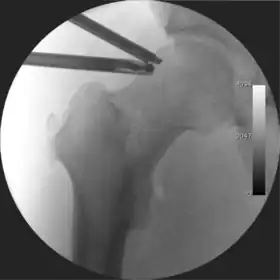

Figure 3. Fluoroscopic picture showing a mild amount of distraction of the hip before insertion of any instruments

The procedure is performed with the patient asleep (general anaesthetic) or under spinal anaesthesia. There are two widely used methods, one with the patient on their back (supine) and the other on their side (lateral decubitus). Which is used is down to the surgeon's preference. To gain access to the central compartment of the hip joint (between the ball and socket), traction is applied to the affected leg after placing the foot into a special boot. (See fig. 2) There is specifically designed equipment for this, although some surgeons use a 'traction table', initially designed to help in the operative fixation of broken thigh and lower leg bones. The amount of traction (or pull) needed is assessed with the help of fluoroscopy (low-dose portable x-ray). (See fig. 3) It is usually not possible to distract the ball from the socket with traction alone by more than a few millimetres. Once the surgeon is happy that they will be able to gain access to the hip joint (i.e. the ball will distract from the socket by a small amount), the patient is then painted with antiseptic and the surgical drapes applied.